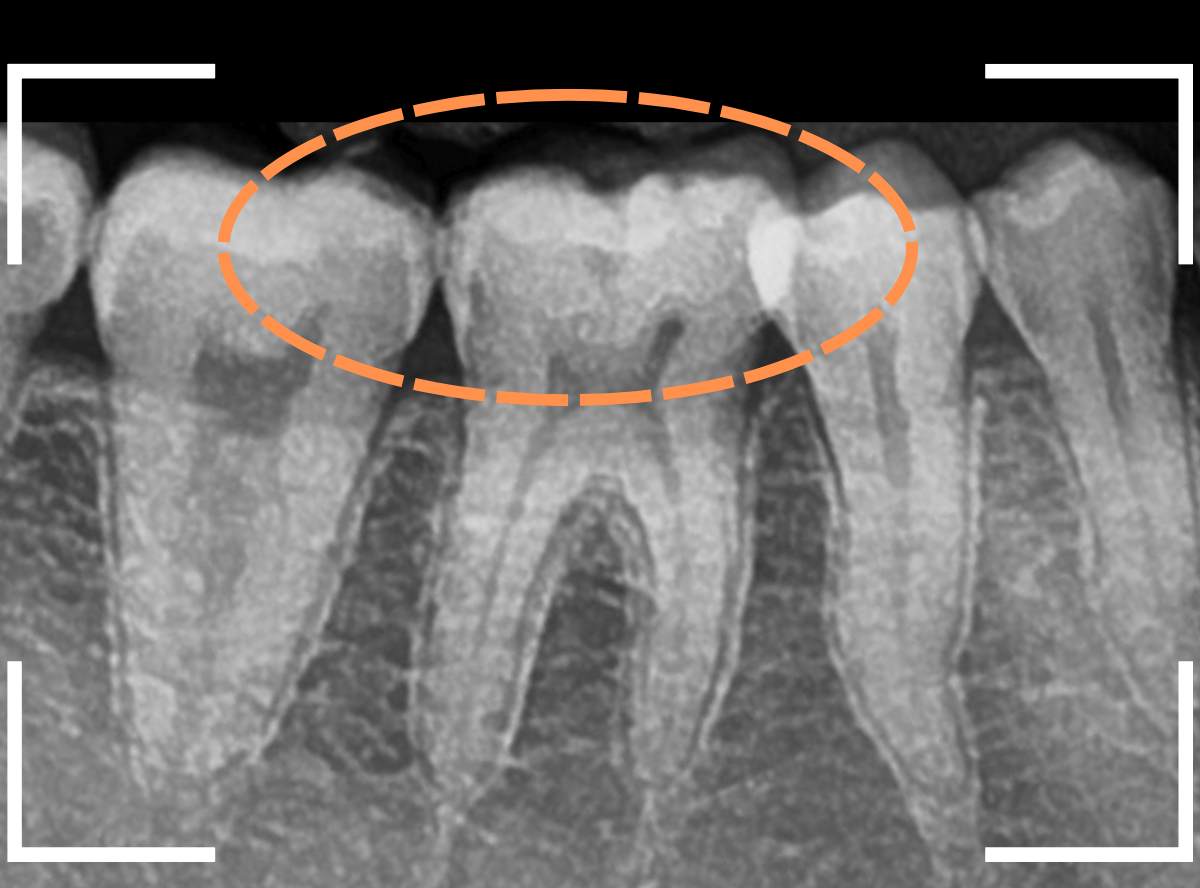

Case.17 レントゲンにはっきり写らないレジンの中の虫歯を削って調べる2

今回も、下の奥歯の虫歯を治療した例です。

特に症状はありませんが、以前に治療したレジンが劣化してすり減っているのと、少し中が黒く透けて見えて、虫歯になっているのが怪しいです。

青いラインが歯の神経です。

以前の虫歯が深めだったようで、レジンが深めにつめてあるのがわかります。

その下がうっすらと虫歯っぽい影になっています(赤いライン)。

虫歯になっているか微妙なラインですが、レジンも劣化していますので、患者さんにご説明して治療することになりました。

レントゲンで虫歯と思われる部分をレジンを除去しました。

見た目には虫歯かどうかはっきりわかりません。

う蝕検知液で染め出します。

うっすらと赤く染色されました。

レントゲン写真と同じく、レジンの下で静かに虫歯が進行し始めていたようです。

もともと深めの虫歯だった部分なので、早いうちに治療が進められてよかったです。